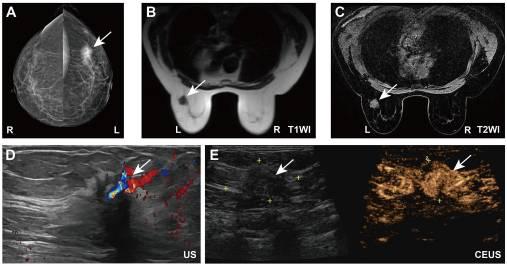

乳房X线摄影显示,左乳房上外象限有一个高密度、不规则形状的肿块,大小约为35×24 mm,边缘呈毛刺状,内部钙化(图1A)。此外,乳腺MRI显示左乳腺上外象限有一个约20×18mm的肿块,形状不规则,边缘呈毛刺状。T1加权图像显示病变信号强度低,脂肪饱和T2加权图像显示混合信号,对比增强图像显示显著增强(图1B和C)。此外,彩色多普勒乳腺超声显示,在左乳房2-3点钟位置距离乳头4厘米处有一个低回声结节,尺寸约为20×14毫米(图1D)。注射造影剂后,病变大小为35×17 mm,表现出不均匀的高增强和突出的血管结构(图1E)。穿刺活组织检查显示左乳房存在侵袭性乳腺癌症(图S1A和B)。免疫组织化学(IHC)结果显示,活检样本细胞Ki-67呈阳性(30%)(超过14%阈值),雌激素受体(ER)呈强阳性(90%),孕激素受体(PR)呈中度至强阳性(30%),人表皮生长因子受体2(HER2)呈阴性(1+)(图S1C-F)。其他术前检查,包括胸部和腹部计算机断层扫描(CT)、颅脑CT和全身骨扫描,均未发现远处转移或异常的证据。血清肿瘤标志物水平也被评估并证明在正常范围内:癌胚抗原(CEA)为2.64 ng/ml(参考值,<4.7 ng/ml),癌症抗原15-3(CA15-3)为18.9 U/ml(参考值<26.2 U/ml)。最初诊断为左侧乳腺癌(管腔B型,cT2N0M0,IIA期)。肿瘤直径>2cm,没有临床明显的腋窝淋巴结受累,也没有远处转移的迹象,与IIA(cT2N0M0)的临床分期一致。根据这些发现以及免疫组织化学分析的结果,肿瘤被归类为管腔B分子亚型。

图1 患者的术前影像学数据。(A)乳房X线摄影。(B)T1和(C)T2加权乳腺磁共振成像。(D)彩色多普勒超声和(E)手术治疗前患者的乳腺超声造影。白色箭头表示肿瘤的位置。CEUS,超声造影